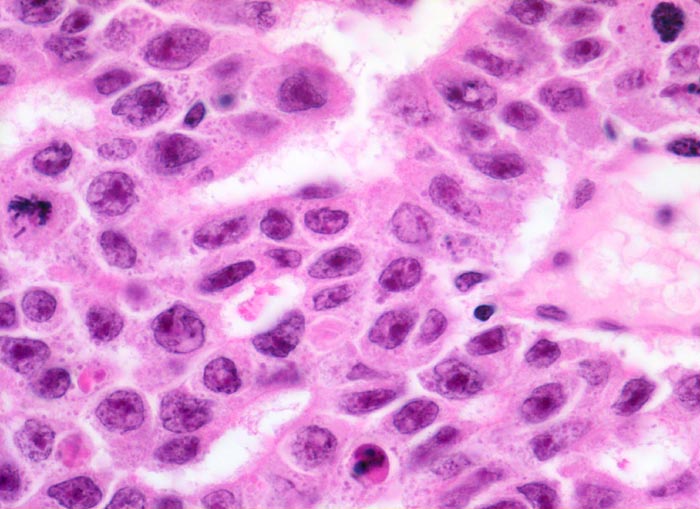

Histologisch bilden die Tumorzellen solide Zellplatten, Drüsen oder papilläre Strukturen mit Einblutungen und Nekrosen. Die Tumorzellen sind polygonal, kubisch oder zylindrisch, haben reichlich Zytoplasma und unscharfe Zellgrenzen. Die grossen Kerne haben grob verklumptes Chromatin und enthalten oft mehrere sehr grosse unregelmässige Nukleolen. Gefässeinbrüche und eine testikuläre intratubuläre Neoplasie sind in der Tumorumgebung häufig nachweisbar

Morphologische Merkmale:

• Sehr grosse, pleomorphe und hyperchromatische Zellkerne mit prominenten Nukleolen.

• Tumornekrosen.

• Mitosen und Apoptosen.

• Reichlich ödematöses Stroma mit einzelnen synzytiotrophoblastären Riesenzellen.